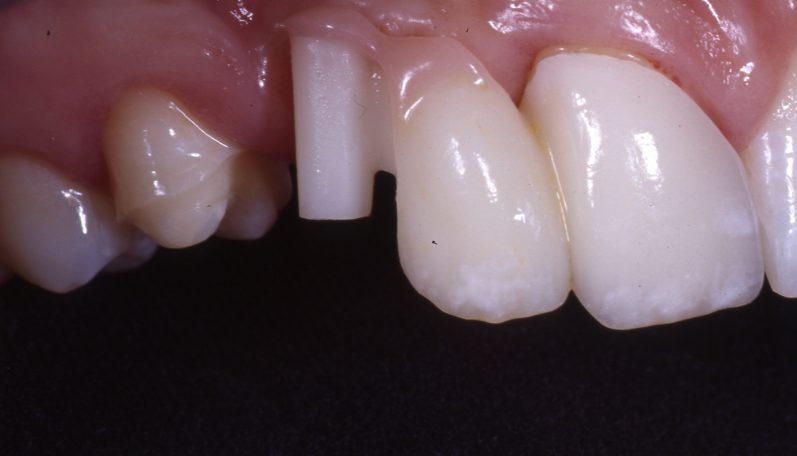

Teleskopierende Oberkieferbrücke mit Vorher- und Nachher-Situation des Patienten.

Teleskopierende Oberkieferbrücke. Wie die eigenen Zähne, aber einfach zu reinigen.